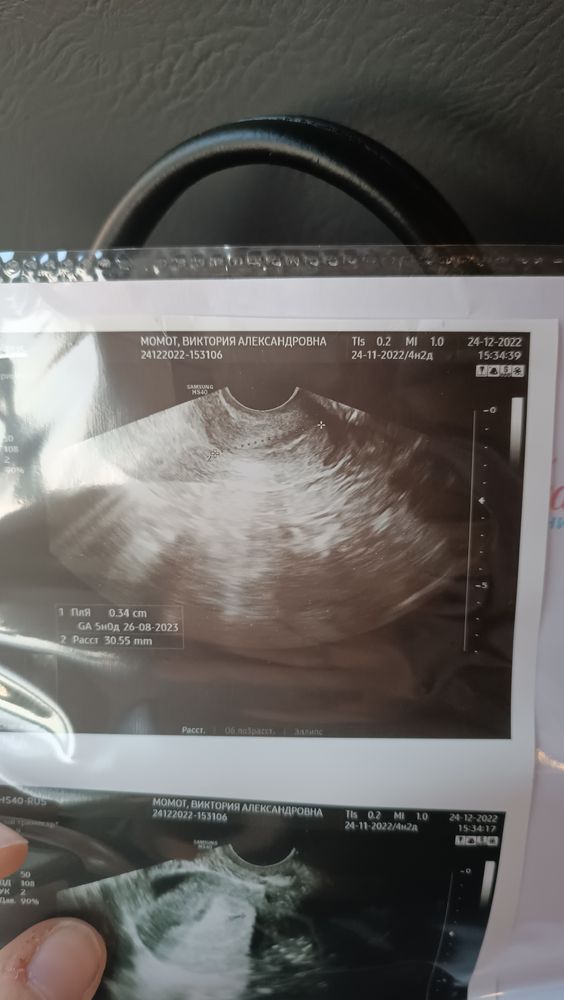

Моё хгч было 32, через 3 дня увидели плодное яйцо 3мм Изображение

Вика, у меня увидели плодное яйцо 3 мм после сдачи хгч - 32 Хгч сдала 21 УЗИ 24 Врач и я были в шоке

Видно плодное яйцо после хгч 32 Тест предиктор